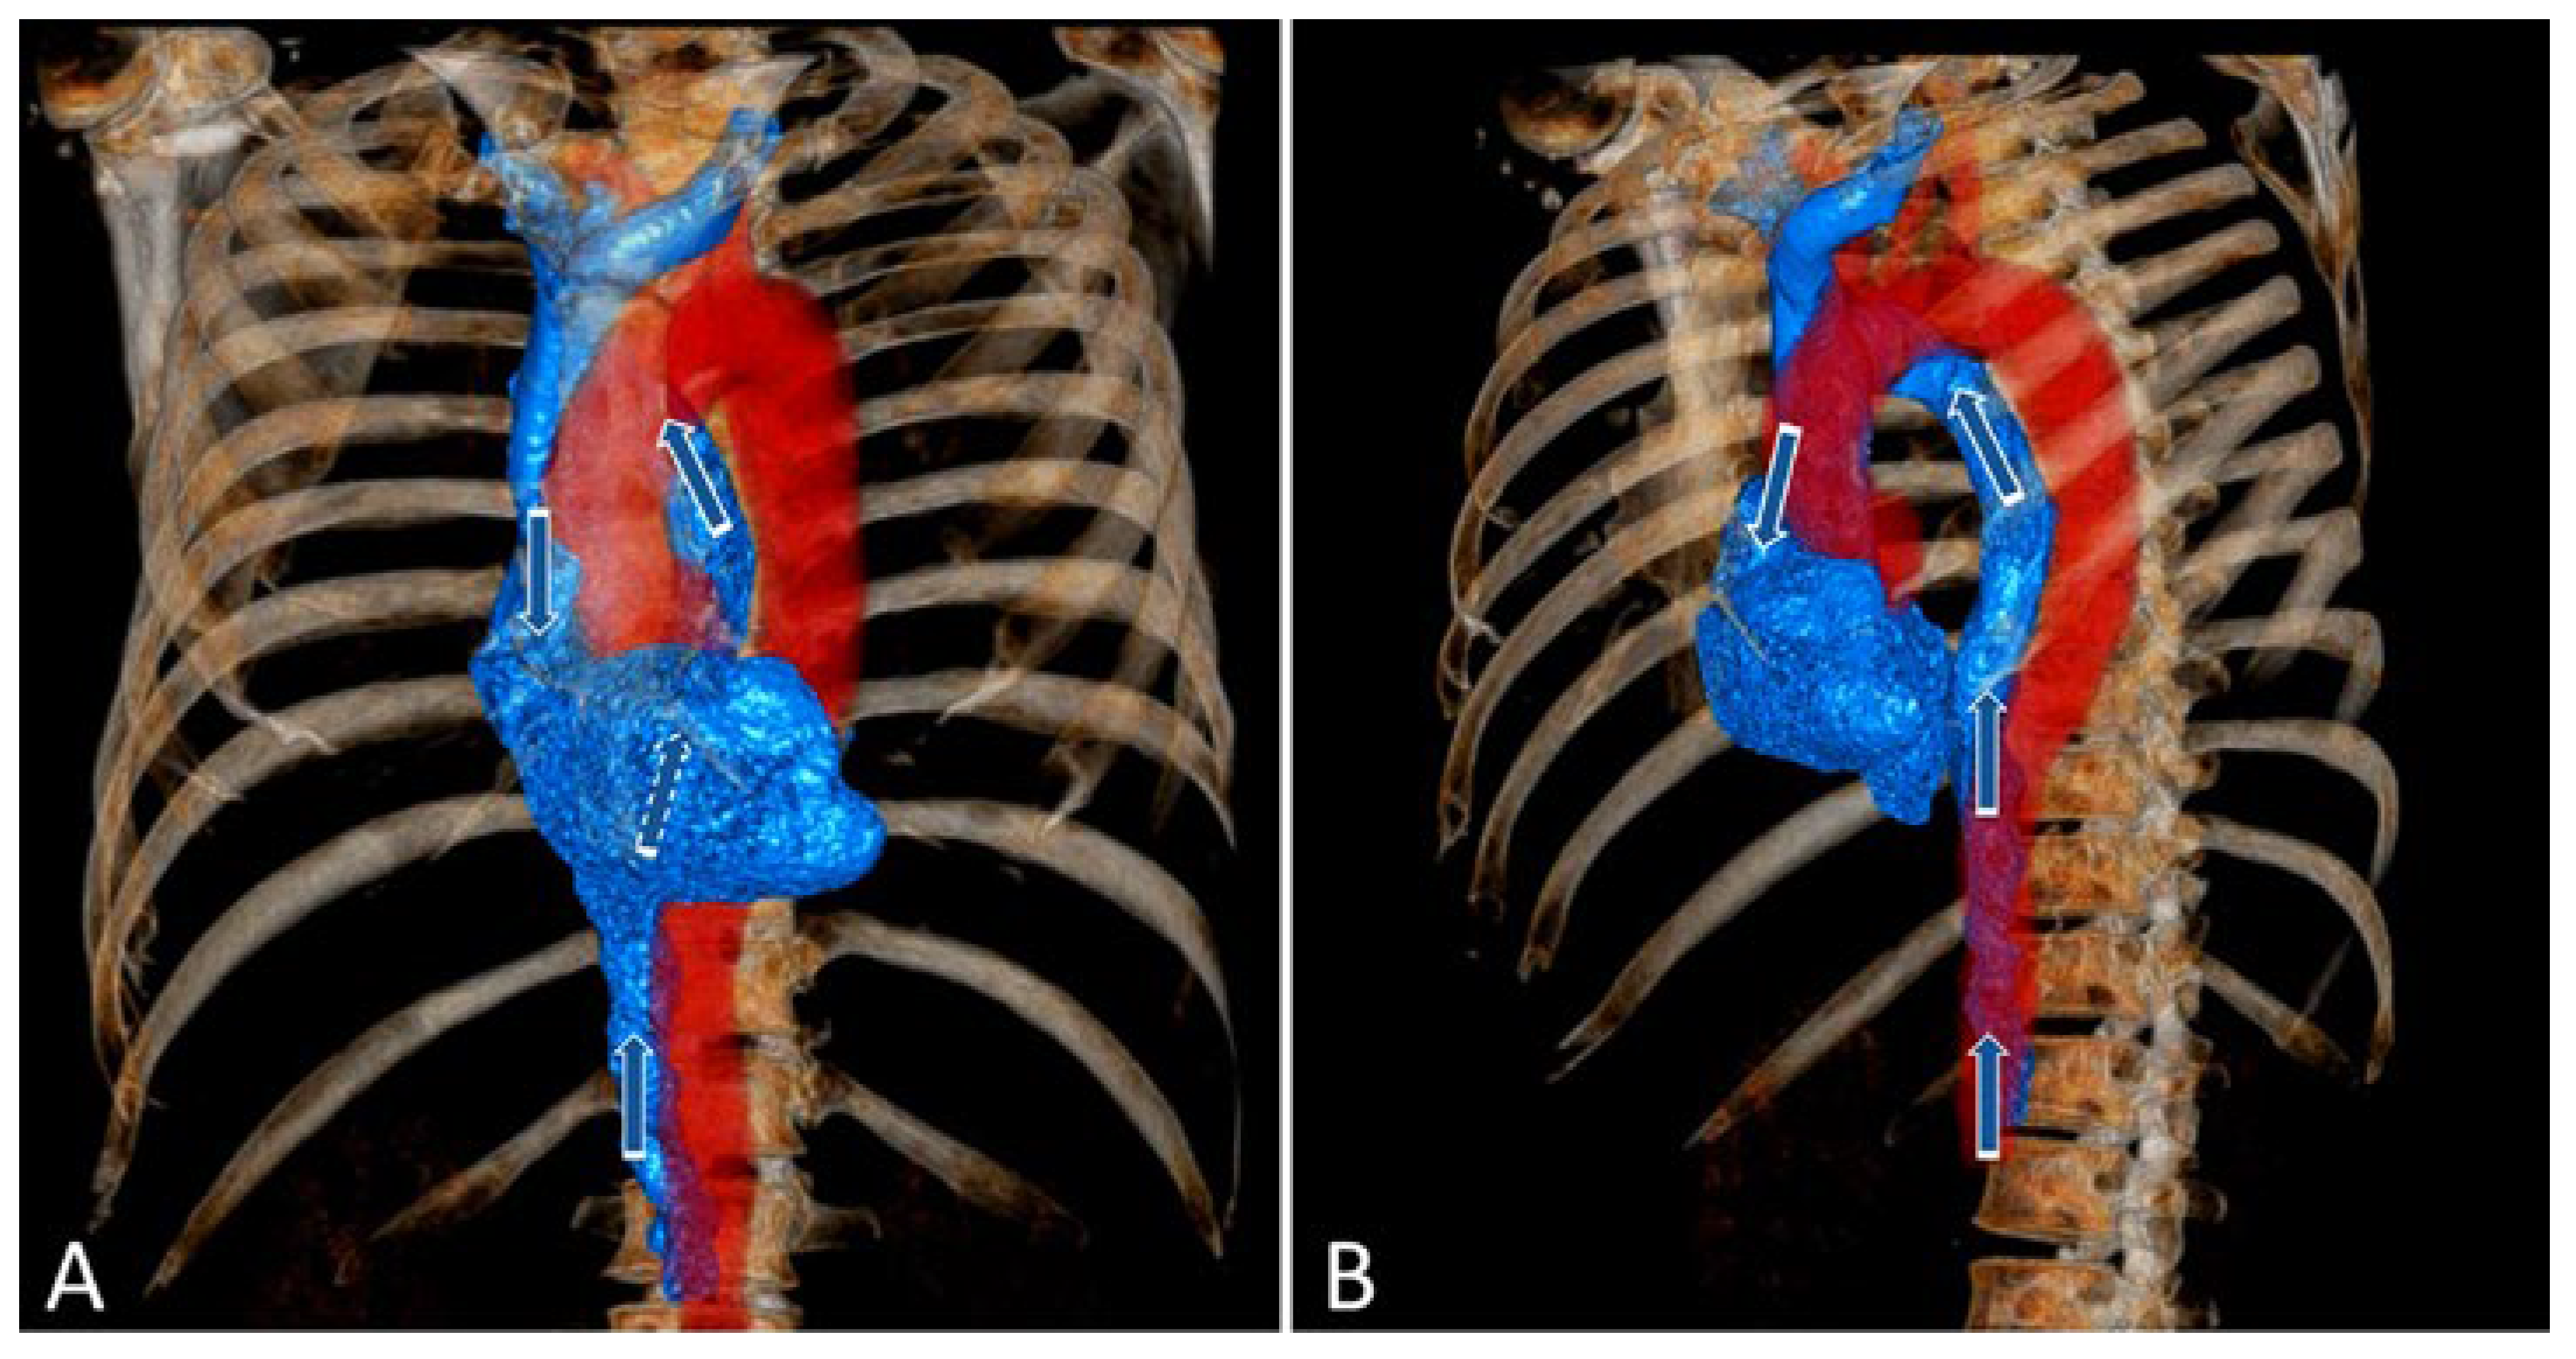

Case description